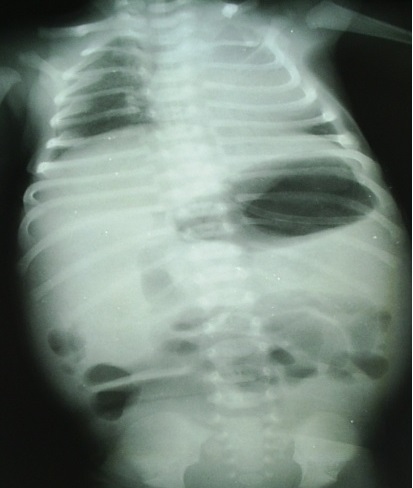

Cliche ASP de face et de profile : Image radiologique

le plus souvent est image de dilatation distendue du colon

avec image de vacuite pelvienne . Dans cas de fistule de

voie urinaire on peut se retrouve de image de la presence de

l'air dans la vessie et tache de calcifie de meconium dans le

colon .

Image radiologique ASP de

face d'une imperfoaration anale cher une nourrison

avec aspect de dilatation gazeuse tres distendue du

colon transverse et colon descendant et de ileon .

Le foie et deux coupole diaprgahmatique sont tres

elevees . Cliche de face ASP , decubitus dorsale |